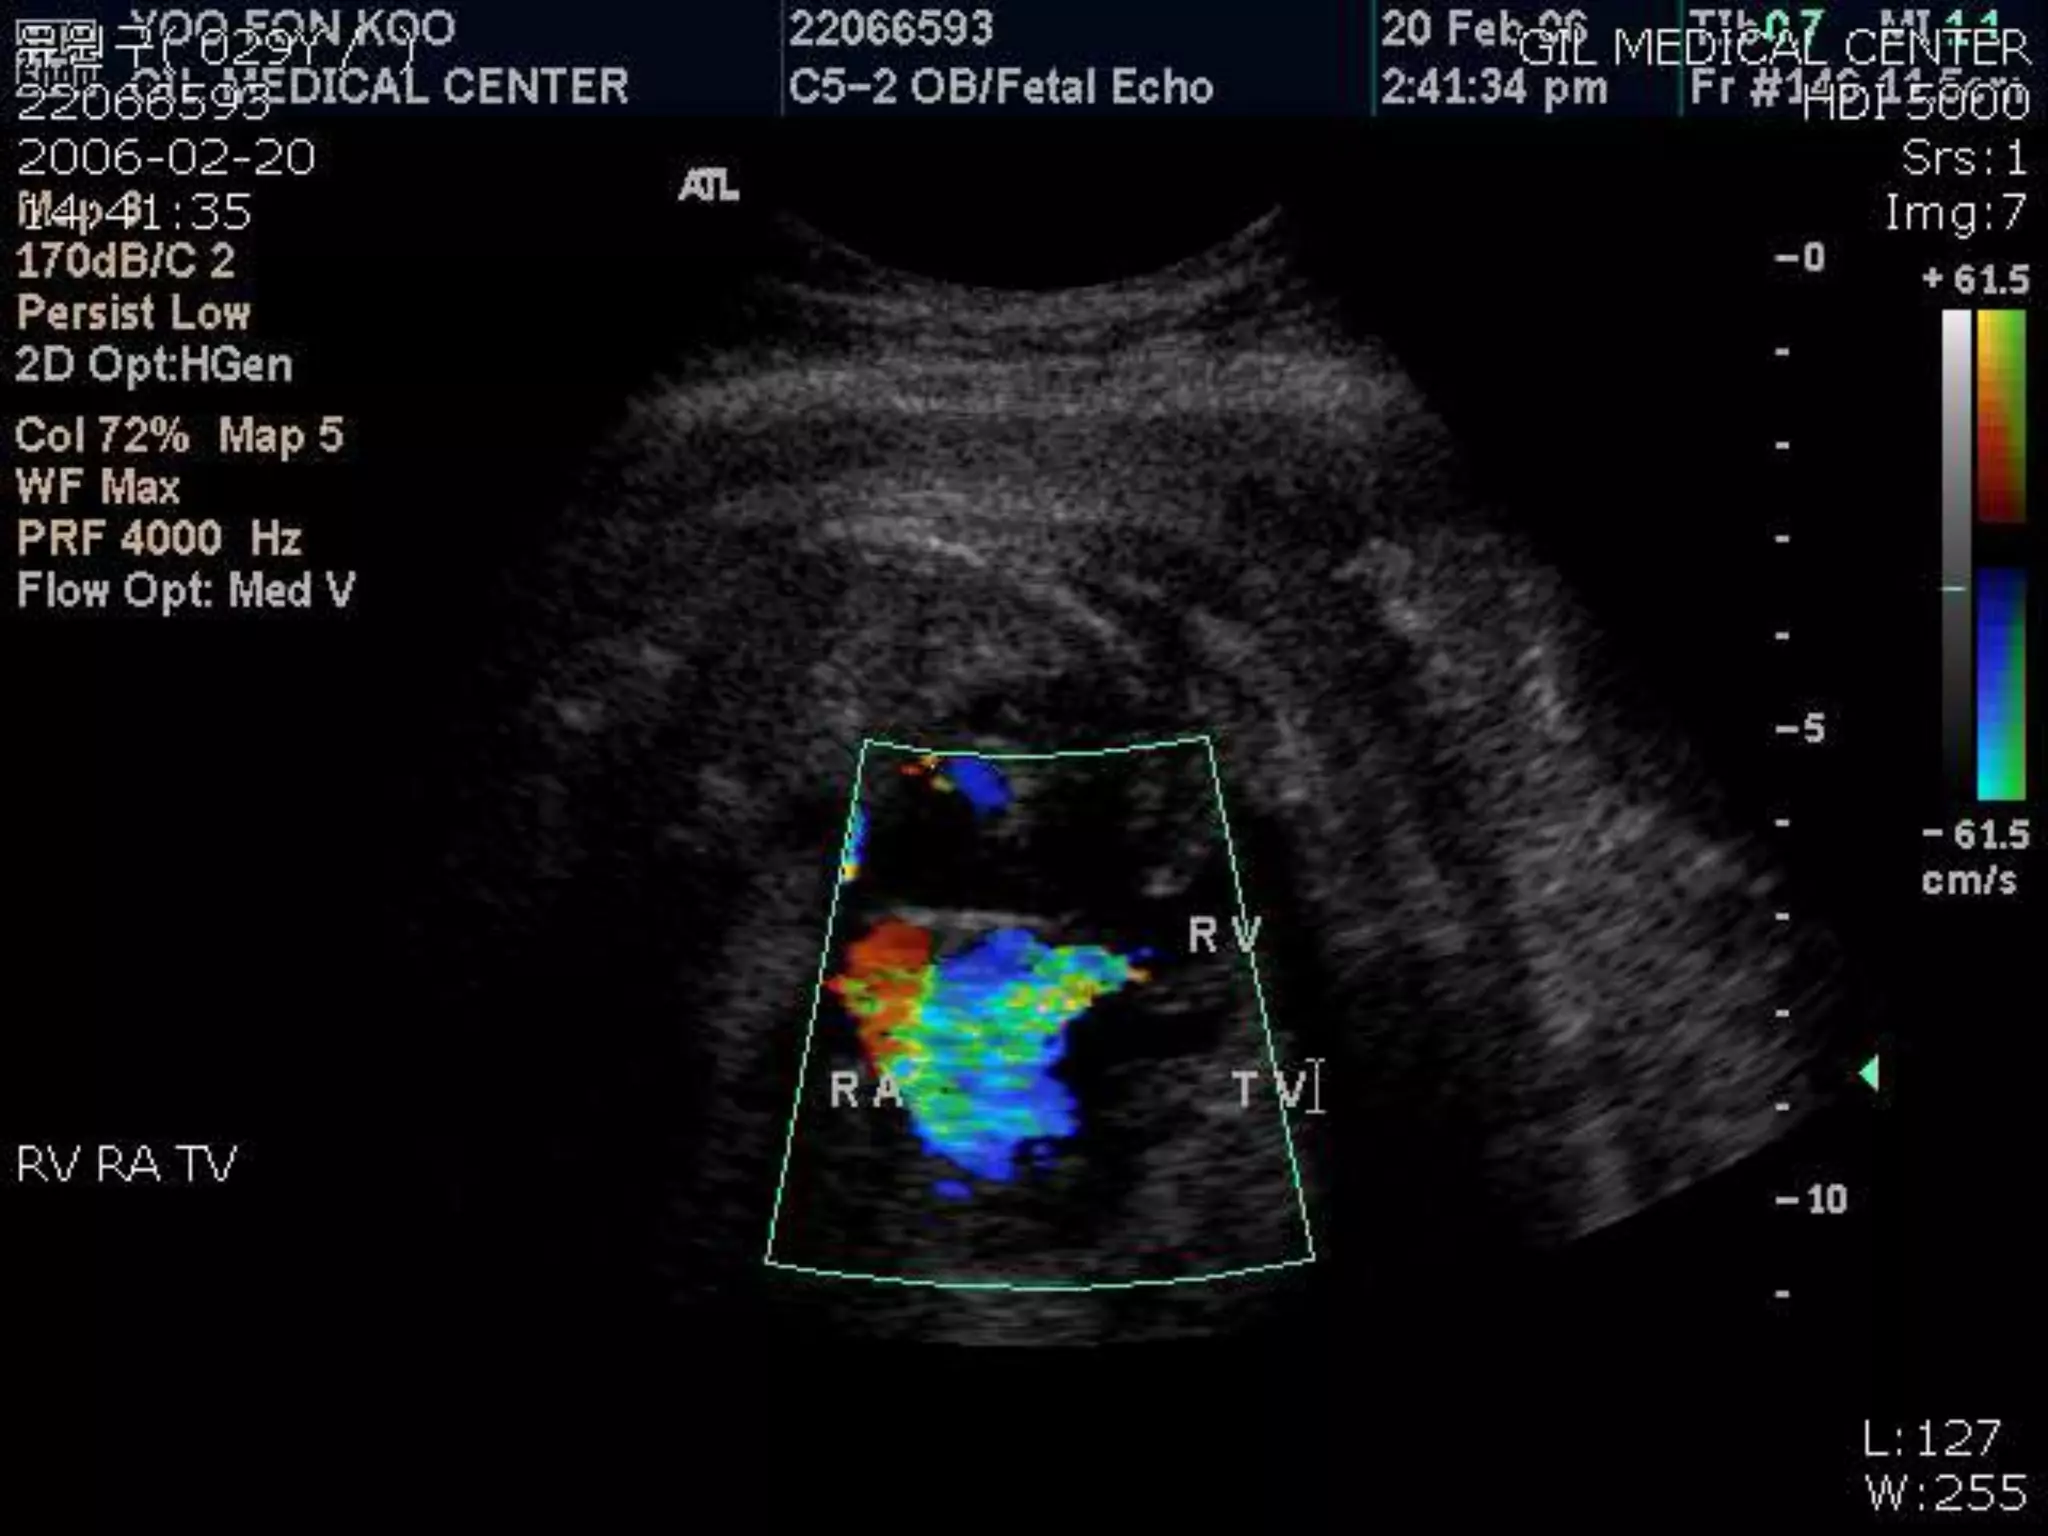

Echocardiogram

 Doppler studies

 Varying degrees of tricuspid regurgitation

 Excludes associated shunts